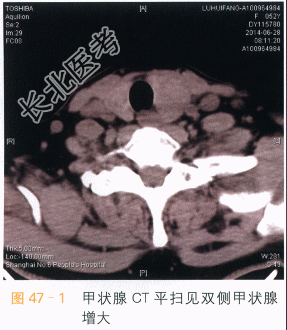

- [材料题] 患者女性,52岁,发现双侧甲状腺结节2年,近期左侧结节增大。体格检查:双侧甲状腺增大,内部扪及多个结节,质韧,活动。实验室和辅助检查TSH5.59IU/ml,T、T正常。超声:双侧甲状腺多个混合性回声结节,形态规则,边缘尚清。左侧结节CDFI未见血流。右侧结节少许血流信号。影像学资料如图所示。

- 简答题1、请问该患者的影像诊断是什么?